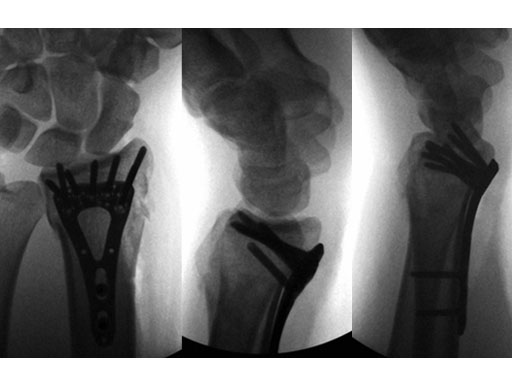

22-year-old male fell off a horse while playing polo.

Case provided by Ladislav Nagy, Zrich, CH

Fig 3ac Immediate postoperative x-rays.